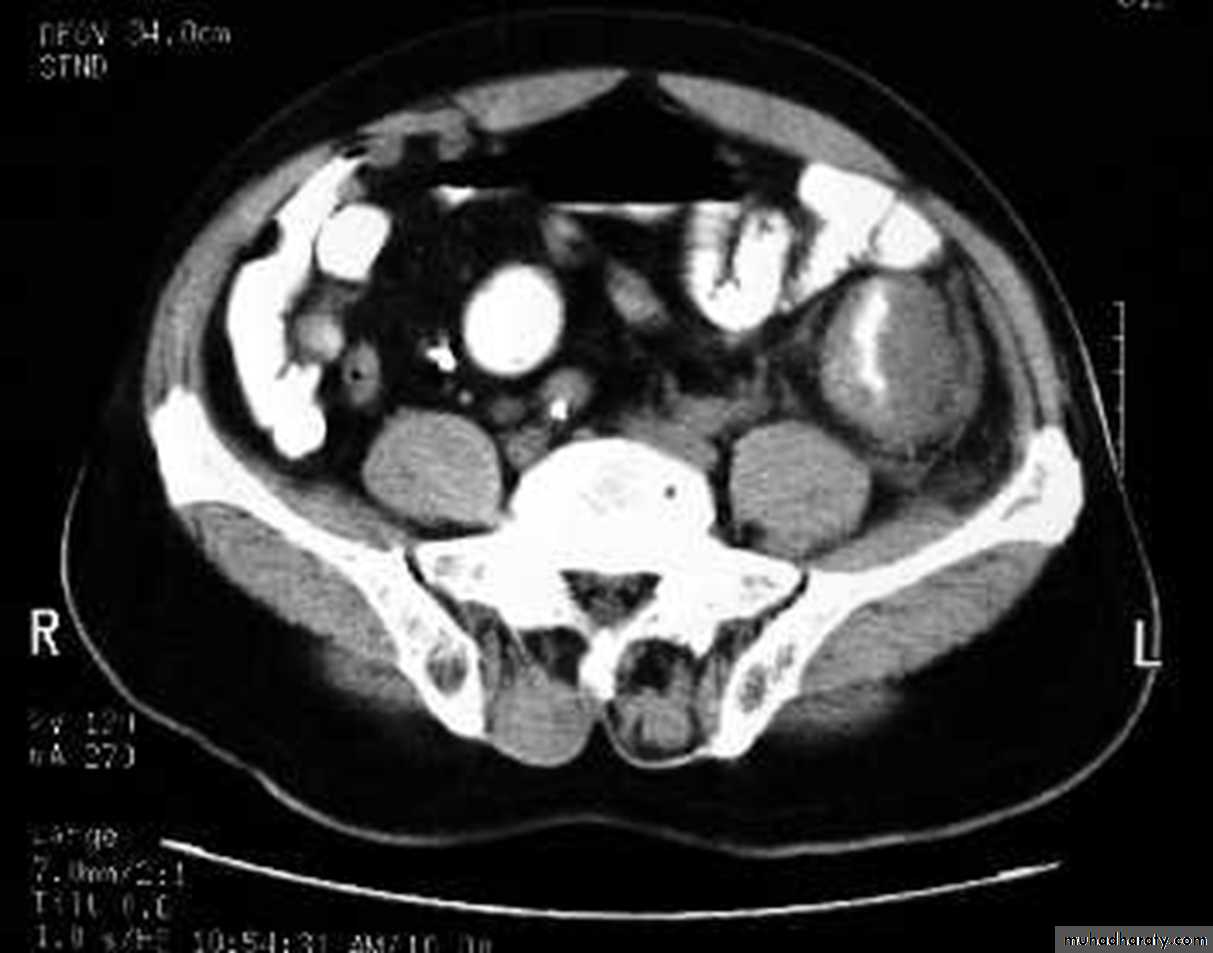

apple core lesion in the descending colon

Multiple lesions are seen in the liver and spleen consistent with metastases